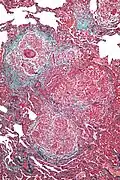

High magnification photomicrograph of a lung biopsy taken showing chronic hypersensitivity pneumonitis (H&E), showing mild thickening of the walls of the small air sacs by invasion of white blood cells. A multinucleated giant cell, seen within the walls of the air sacs to the right of the picture halfway down, is an important clue to the correct diagnosis.

Low magnification view of the histology of chronic hypersensitivity pneumonitis. The interstitium is expanded by a chronic inflammatory infiltrate. Two multinucleated giant cells can be seen within the interstitium at left, and a plug of organizing pneumonia at bottom left.

Lung biopsies can be diagnostic in cases of chronic hypersensitivity pneumonitis, or may help to suggest the diagnosis and trigger or intensify the search for an allergen. The main feature of chronic hypersensitivity pneumonitis on lung biopsies is expansion of the interstitium by lymphocytes accompanied by an occasional multinucleated giant cell or loose granuloma.[7][22]

When fibrosis develops in chronic hypersensitivity pneumonitis, the differential diagnosis in lung biopsies includes the idiopathic interstitial pneumonias.[23] This group of diseases includes usual interstitial pneumonia, non-specific interstitial pneumonia and cryptogenic organizing pneumonia, among others.[7][22]

The prognosis of some idiopathic interstitial pneumonias, e.g. idiopathic usual interstitial pneumonia (i.e. idiopathic pulmonary fibrosis), are very poor and the treatments of little help. This contrasts the prognosis (and treatment) for hypersensitivity pneumonitis, which is generally fairly good if the allergen is identified and exposures to it significantly reduced or eliminated. Thus, a lung biopsy, in some cases, may make a decisive difference.